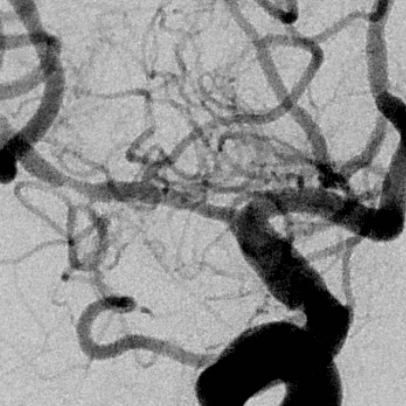

右侧MCA长节段血管变细狭长

长节段MCA血管狭长变细,尤以近端为重

乍一看血管似乎还可以

放大后仔细观看,近端有局限性血管变细,并见双腔征

另外时相远端也隐约局限性变细